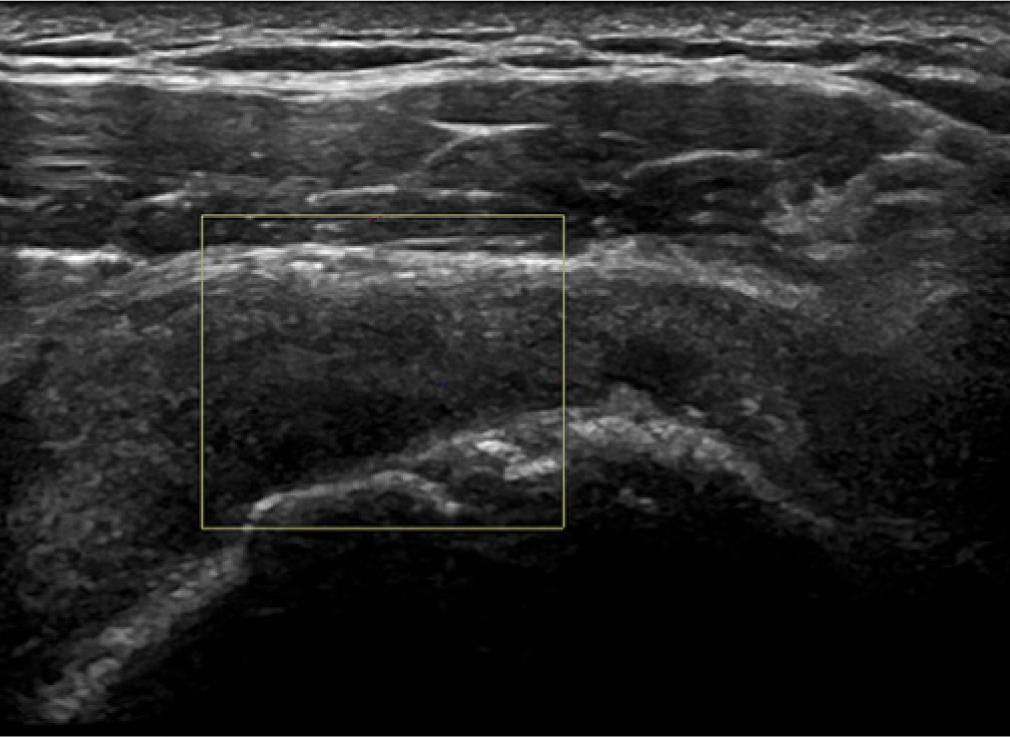

The bursa should be seen as three parallel stripes. The top and bottom should be of high echogenicity compared to the low central stripe (Fig. 1). If the lower stripe is not seen, then this would imply a bursal surface supraspinatus or infraspinatus fraying (Fig. 2). If the stripes are not clear in outline, appearing blurred, then the presence of an adhesive bursitis should be considered (Fig. 3). In a child or young adult, the central stripe may be very thin, and the bursa may appear as one stripe if the resolution of the ultrasound machine is poor.

The upper layer of the supraspinatus tendon is missing